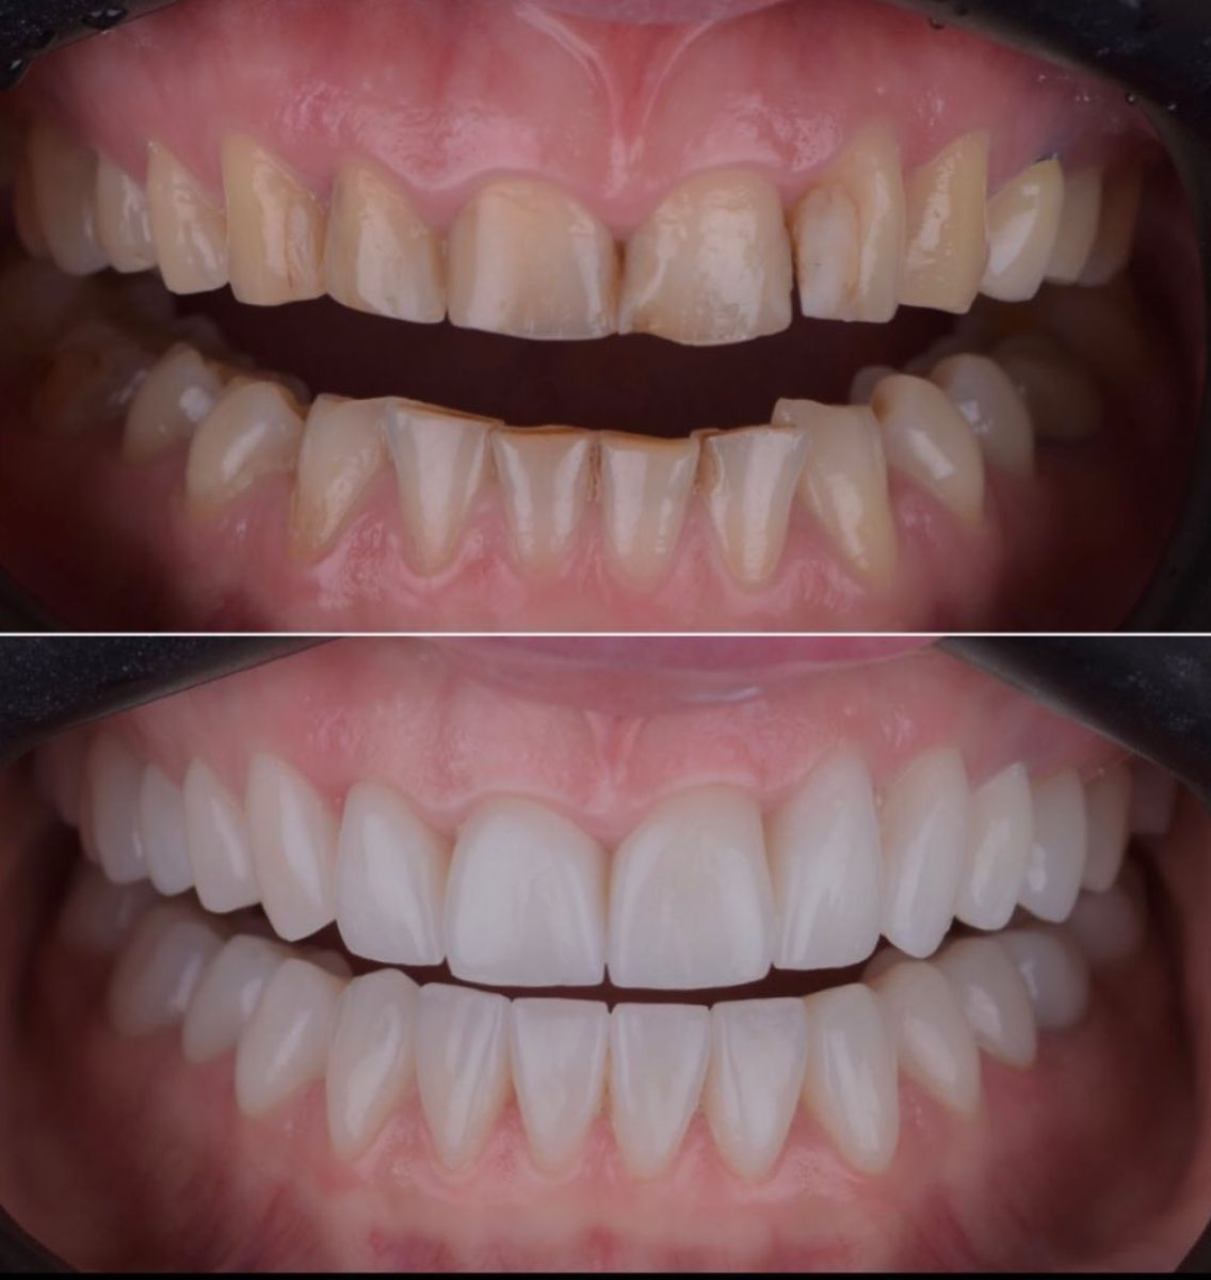

Ljuskice za zube - Veneers

Ljuskice su estetsko rješenje koje vam omogućuje da transformirate svoj osmijeh, trajno se lijepe na prednju površinu zuba i prekrivaju nepravilnosti u obliku, sitne pukotine, diskoloracije ili razmake između zuba.

Koristeći specijalizirane dizajnerske programe i modernu 3D tehnologiju, izrada ljuskica omogućuje precizno reproduciranje karakteristika prirodnih zuba. Osim za estetske razloge, koriste se i kod ispravljanja nepravilnog zagriza i narušene okluzije.

Postavljanje ljuskica je brzo i jednostavno, a rezultati su odmah vidljivi. Vaši zubi će izgledati prirodno lijepo, a vi ćete se osjećati samopouzdano svaki put kada se nasmijete!

Veneers at Dental Clinic Ćatović in Pula

Private dental practice DENTAL CLINIC ĆATOVIĆ in Pula offers a comprehensive range of services including implantology, prosthodontics, oral surgery, and endodontics. For those seeking to enhance their smiles, we specialize in veneers, the ultimate solution for achieving a radiant and flawless smile.

Whether you're dealing with discoloration, chipped or misaligned teeth, or gaps between your teeth, veneers can address these issues and give you the smile you've always dreamed of.

Our experienced team at DENTAL CLINIC ĆATOVIĆ utilizes the latest techniques and technologies to ensure precise and long-lasting results. With veneers, you can achieve a natural-looking smile that complements your facial features and boosts your confidence. For more information on our services, call us or visit our official website.